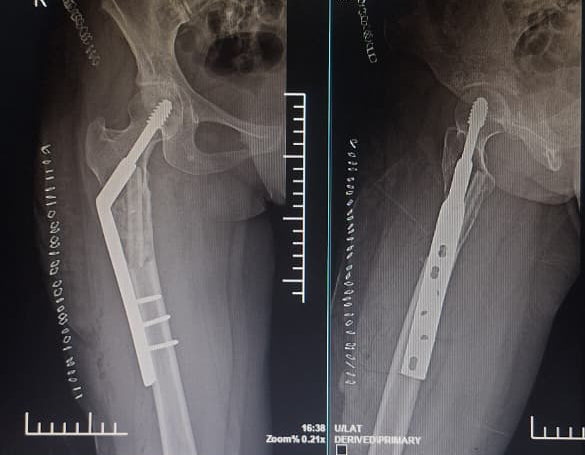

In 2022, the patient presented with progressive pain and restricted range of motion of the right hip following minor trauma. She was re-evaluated clinically and imaging was done. Radiographs (Fig 4 ) and MRI (Fig 5) revealed an expansile lytic lesion of the right proximal femur consistent with intraosseous hemangioma. Due to risk of pathological fracture we planned for fixation of right proximal femur. She underwent right proximal femoral bone excision biopsy and dynamic hip screw fixation with iliac–fibular strut bone grafting (Fig 6). Post-operative period was uneventful. Started partial weight bearing after 45 days followed by full weight bearing by 90 days. Very good radiological incorporation of graft noted and fixation was stable radiologically (Fig 7). Histopathology report suggestive of benign bone hemangiomatous tissue without any features of malignancy (Fig 8).

• 2022: Lytic right proximal femur lesion with risk of pathological fracture (Fig 4).

• Postoperative consolidation of proximal femoral graft (Fig 7).

Intervention

The patient underwent right proximal femur bone excision biopsy, dynamic hip screw fixation, and iliac–fibular strut bone grafting to prevent structural collapse and improve mechanical stability (Fig 6). Post-operative imaging confirmed adequate consolidation over 3 year follow-up period (Fig 10).

Figure 7